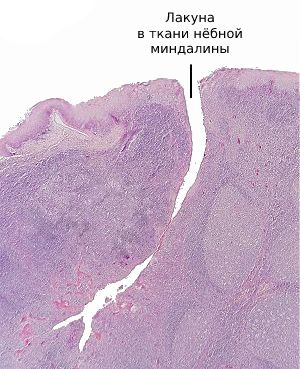

К развитию паратонзиллярного абсцесса предрасполагает сложное строение нёбных миндалин: они состоят из множества углублённых карманов (лакун), которые расположены в толще ткани и визуально напоминают фьорды.

Глубина лакун может достигать двух-трёх сантиметров. Их поверхность выстлана железами Вебера, которые механически очищают миндалины во время артикуляции, жевания и сжимания миндалин мышцами глотки при глотании, что можно сравнить с выжиманием рукой поролоновой губки.

![Лакуна в ткани нёбной миндалины [11]](/pimg3/opredelenie-lokalizatsii-abstsessa-F2E1.jpeg)

Снижение иммунитета, заражение патогенными бактериями, чаще всего бета-гемолитическим стрептококком, рубцы нёбных миндалин при длительном хроническом тонзиллите приводят к закупорке выводного протока желёз Вебера. Воспалительный отёк не позволяет продуктам жизнедеятельности бактерией и погибшим лимфоцитам выйти наружу в ротовую полость. В результате в ближайшей к нёбным миндалинам рыхлой клетчатке скапливается гной, который не может адекватно выйти наружу [9] [12] .